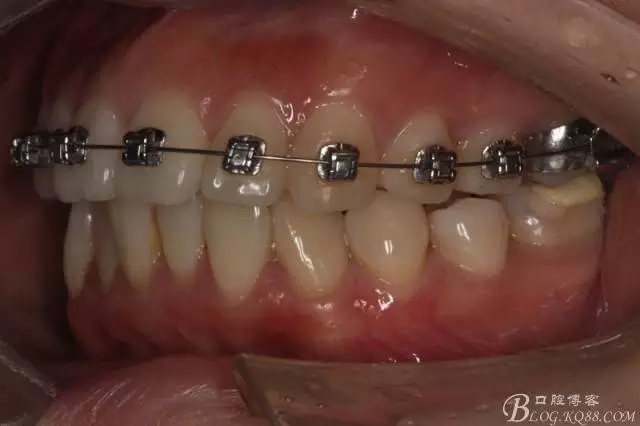

患者,女,主訴:牙齒不齊。

如圖,該病例為簡單排齊病例,但77鎖合是矯治中的關(guān)鍵所在,你會(huì)怎么處理?

該病例主要為17、27頰側(cè)位同時(shí)伴有伸長,當(dāng)然種植支抗可以解決,但還有簡單實(shí)用的辦法嗎?如圖,在橫腭桿遠(yuǎn)中延伸出牽引鉤,位置盡量遠(yuǎn)離合平面,7粘舌側(cè)扣,牽引力的方向?yàn)閴旱图吧嘞?,下圖為兩個(gè)月的效果,17已到位,27還未到位。